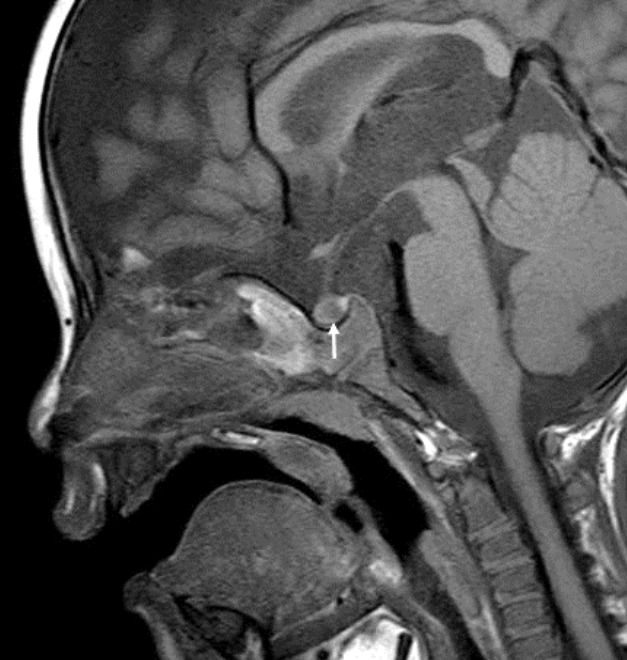

骨龄 X 线照片显示实际年龄为 4 岁 8 个月。 使用 Greulich 和 Pyle 方法测定骨龄为 3 岁。